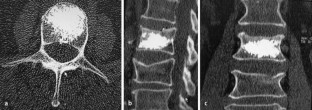

Wir haben in einer prospektiven Studie 92 Wirbelkörper (Th8–L5) bei 60 Patienten im Alter von 76,8 (60–95) Jahren in linksmonopedikulärer Technik über einen para-/transpedikulären Zugang augmentiert und eine Auswertung der Kanülenposition, applizierbaren Zementmenge sowie eine CT-gestützte Analyse der Zementverteilung durchgeführt. Hierzu wurde der Wirbel in der Frontalebene in 9 Segmente unterteilt. Die Kanüle wurde in 85,9% (79/92) im mittleren, in 11,9% (11/92) im rechten und in 2,2% (2/92) im linken Wirbelkörperdrittel platziert. Punktionsassoziierte Komplikationen wurden nicht beobachtet. Das applizierte Zementvolumen lag bei 4,5 (1,5–9,0) ml.

We present a prospective study on 92 vertebral body fractures (Th8–L5) in 60 patients, aged 76.8 (60–95) years, which were treated by unipedicular vertebroplasty using a para-/transpedicular approach. We evaluated needle position, injected cement volume, and cement deposition based on CT scans. The vertebral body was divided into nine segments in a frontal plane view. The needle was placed in the middle third in 85.9% (79/92), in the right in 11.9% (11/92), and in the left third in 2.2% (2/92). Complications associated with cannulation were not observed. The injectable cement volume was 4.5 (1.5–9.0) ml.

Abb. 1